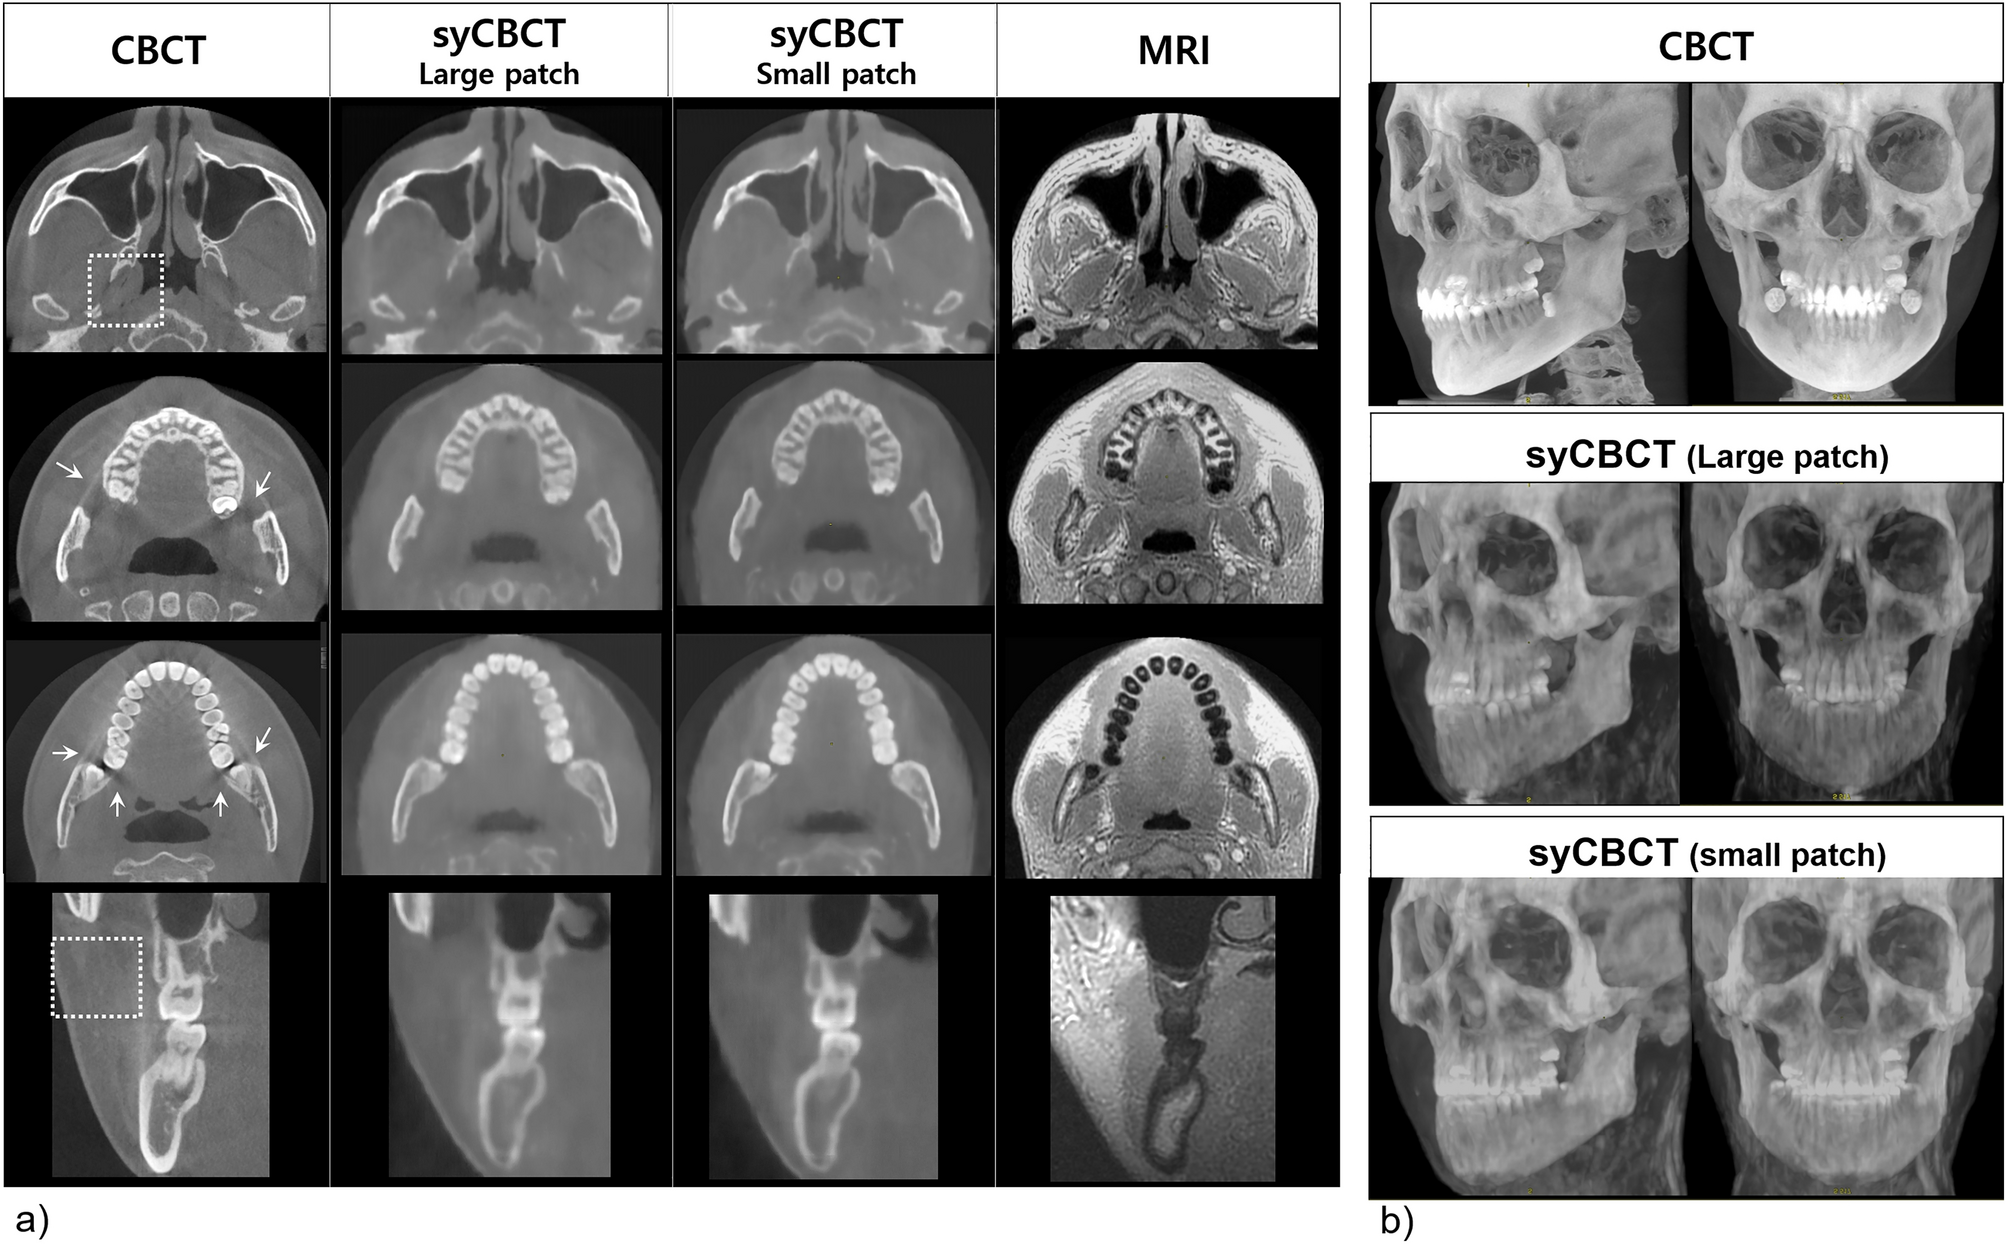

Figure 5

(a) The axial and cross-sectional images show the soft tissue of syCBCT with less noise, whereas more heterogeneity is observed in CBCT (dotted box). The scattering artifact (arrow) in the CBCT image is not evident in the syCBCT image. The margin of tooth structure is blurred in syCBCT. (b) Three-dimensional reconstruction of CBCT and syCBCT using the maximum intensity projection method. CBCT, cone-beam computed tomography; syCBCT, synthetic CBCT.